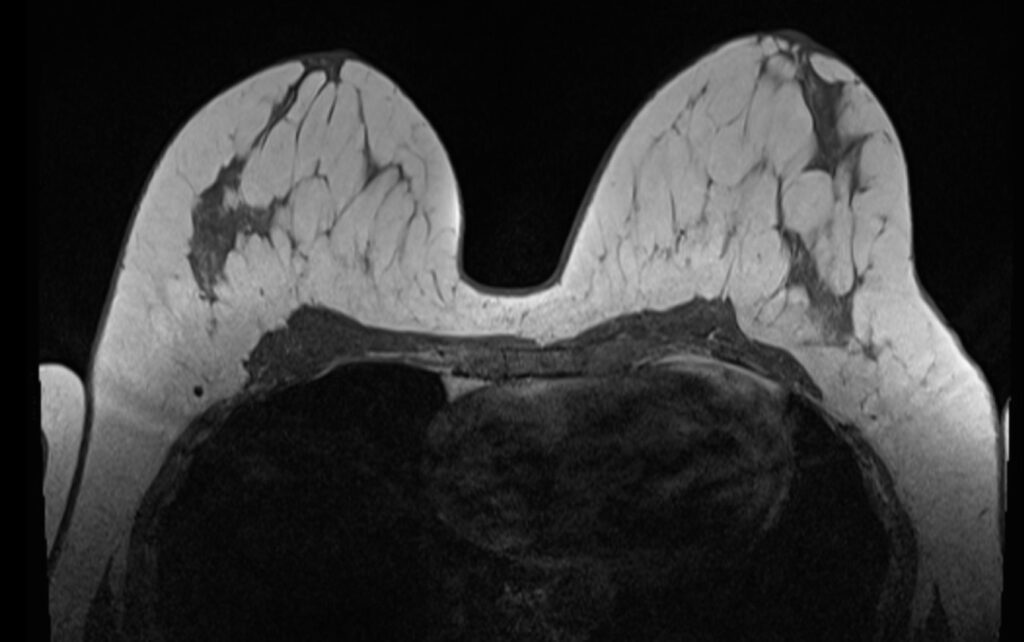

Die Magnetresonanztomographie (MRT) der Brust, auch MRT Mamma genannt, ist eine hochpräzise Untersuchung, die besonders zur Früherkennung, Diagnostik und Therapieplanung von Brustveränderungen eingesetzt wird. Sie bietet eine detaillierte Darstellung des Brustgewebes und wird häufig bei unklaren Befunden oder zur Ergänzung anderer Untersuchungsmethoden wie der Mammografie verwendet. Diese Untersuchung ist strahlungsfrei und eignet sich besonders für Frauen mit dichtem Brustgewebe oder einem erhöhten familiären Risiko für Brustkrebs.

Der Begriff “Mamma” stammt aus dem Lateinischen und bedeutet “Brust” oder “weibliche Brustdrüse”. In der medizinischen Fachsprache wird er häufig verwendet, um Untersuchungen oder Behandlungen im Zusammenhang mit der Brust zu beschreiben, wie z. B. die MRT Mamma. Diese Untersuchung liefert präzise und detaillierte Bilder des Brustgewebes und wird oft zur Früherkennung oder Diagnostik von Brustveränderungen eingesetzt.

In der Tumordiagnostik wird die MRT eingesetzt, um Informationen über Lage und Größe eines Tumors zu gewinnen. Aufgrund des unterschiedlichen Wasserstoffgehaltes ist oftmals eine Unterscheidung zwischen verändertem und gesundem Gewebe möglich. Zumeist wird zur weiteren Unterscheidung, ob eine bösartige Veränderung vorliegt noch ein Kontrastmittel gegeben, welches die unterschiedliche Durchblutung in den Geweben darstellt.